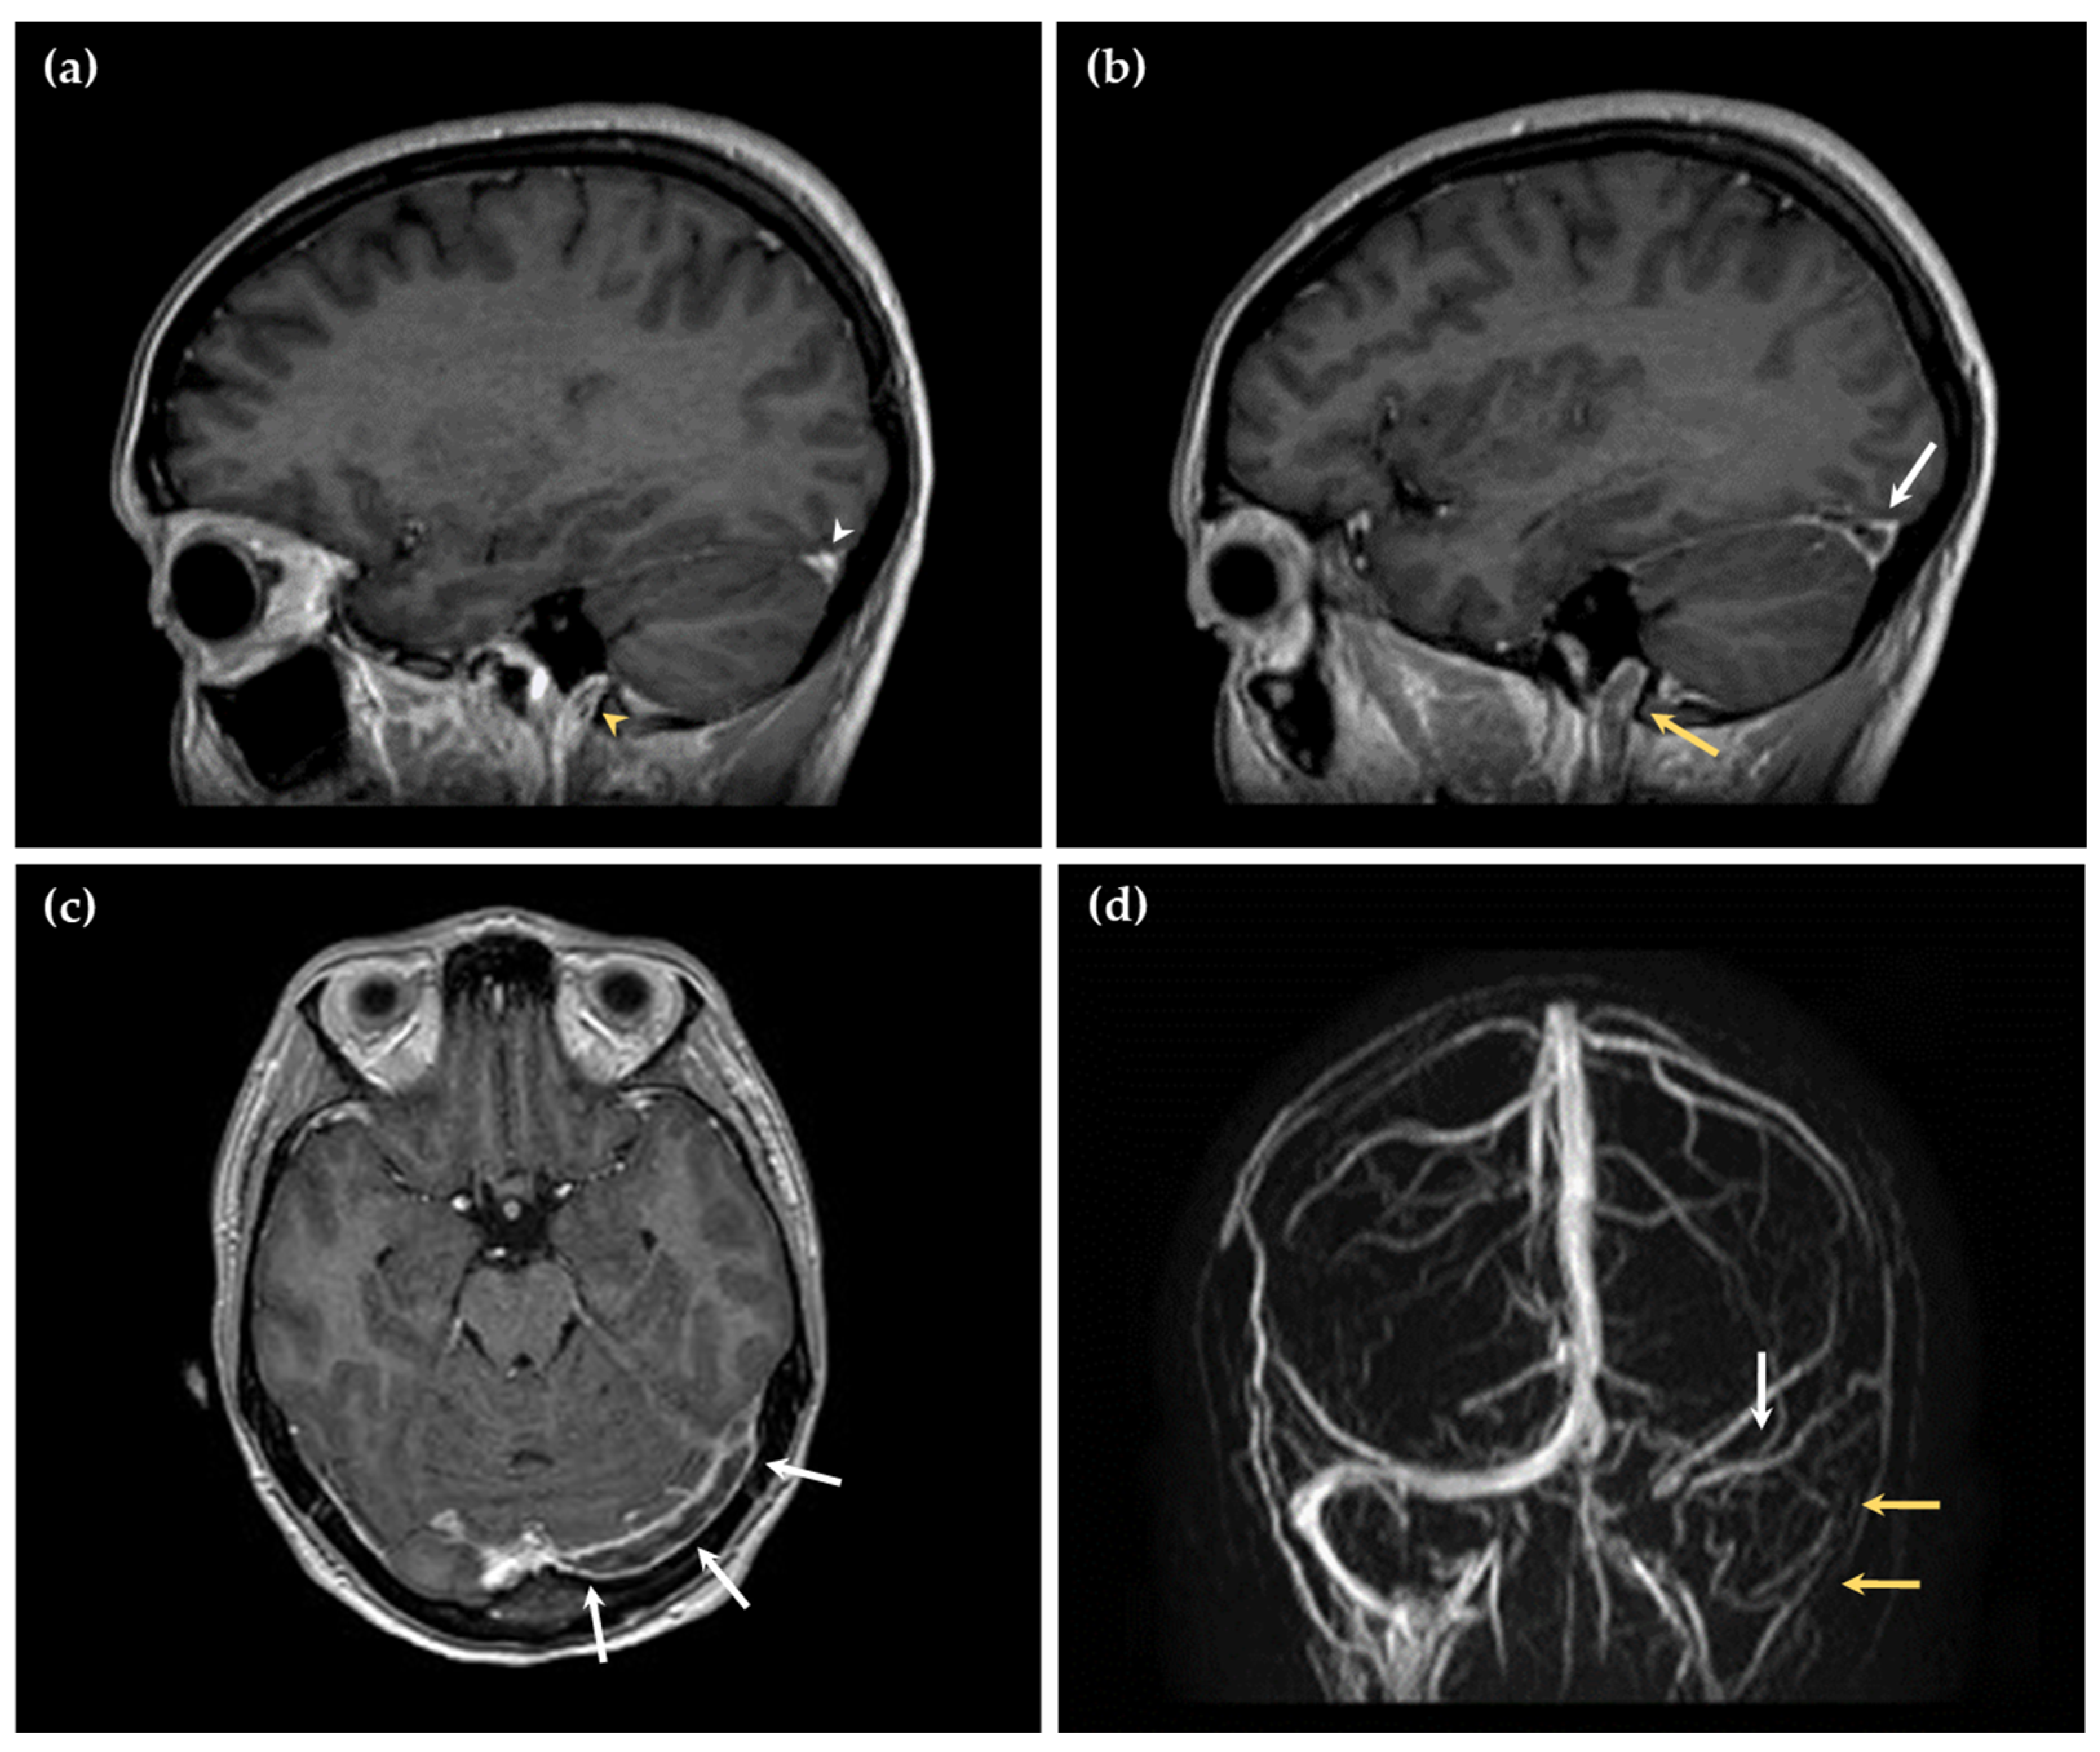

A 21-year-old woman presented to the Emergency and Resuscitation service of our hospital with a headache that was unresponsive to medical treatment. According to her medical history, she was a smoker and was taking the OCP. Her blood pressure was recorded as 108/69 mmHg; her heart rate was 133 bpm; and her body temperature was 36.9 °C. Imaging revealed a massive thrombosis of the cerebral venous sinuses, i.e., the transverse sinus, sigmoid sinus, and internal jugular vein on the left hemisphere, with no parenchymal lesions (Figure 1 and Figure 2).

Figure 2.

Magnetic resonance imaging of the illustrative case history. Sagittal 3D contrast-enhanced T1-weighted images showing (a) normal contrast enhancement in the right transverse sinus (white arrowhead) and internal jugular vein (yellow arrowhead); (b) a filling defect in contrast enhancement in the left transverse sinus (white arrow) and the left internal jugular vein (yellow arrow), indicating cerebral venous thrombosis; (c) axial 3D contrast-enhanced T1-weighted image showing an extensive filling defect in contrast enhancement within the left transverse sinus (white arrows); (d) magnetic resonance venography showing no vascular signal on the left transverse and sigmoid sinus (white arrow) extending to the left internal jugular vein (yellow arrows).